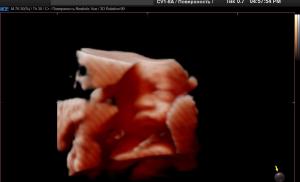

Будущий малыш – видим по-настоящему с Realistic Vue Будущий малыш – видим по-настоящему с Realistic Vue

В чем преимущество аппаратов...